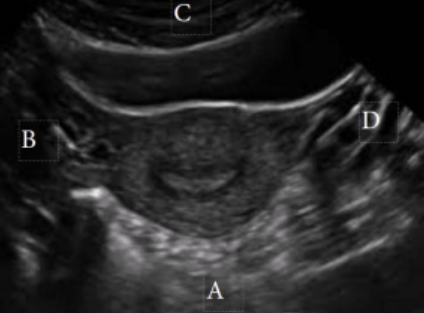

What is letter B in this image?

a. Superior

b. Right

c. Anterior

d. Posterior

Right

What is letter D in this image?

a. Anterior

b. Superior

c. Posterior

d. Inferior

Inferior

What is letter C in this image?

a. Left

b. Posterior

c. Inferior

d. Superior

a. Posterior

b. Left

Posterior